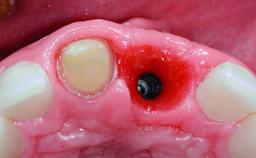

A 30-year-old patient presented at our clinic with a chief complaint of pain in her endodontically treated right maxillary central incisor (tooth 11) with a post-and-core and a fixed single crown. She had a very high lip line, a medium to thin soft-tissue phenotype, and a medium scalloped gingival contour. She also had high esthetic expectations because of her young age and beautiful smile. However, her expectations were realistic and she understood the risks of the treatment. At the initial clinical examination there was a slight mobility of tooth 11; no fistula was observed. The patient also had a single crown on the adjacent tooth 21. Both restorations were old and esthetically deficient. A digital periapical radiograph showed a very small periapical radiolucency, a thick intraradicular post, and no separation between root fragments.

Type of Implants Reduced-Diameter|Two-Piece

Bone Augmentation Staged

Augmentation Materials Xenogenous|Membrane